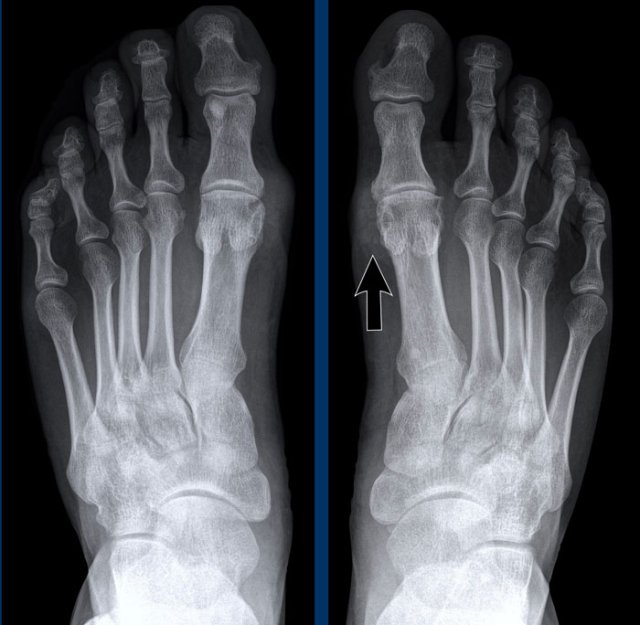

Rheumatoid arthritis in the feet Rheumatoid arthritis in the feet

In this case of rheumatoid arthritis there are marginal erosions adjacent to almost all MTP joints (arrowheads).

The 5th MTP joint is most frequently involved in  rheumatoid arthritis.

When erosions are as severe as in this case, it can look like pencil-in-cup deformity (white arrow) as is frequently seen in psoriatic arthritis.

However, the primarily affected MTP joints distribution and less affected interphalangeal joints is the clue that this is a case of rheumatoid arthritis.